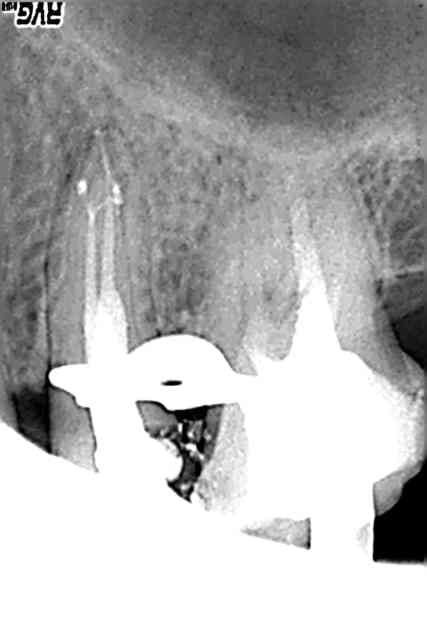

Bon je sais que le fil est lancé sur la mixte, mais comme aujourd'hui j'inaugure le thermaprep qu'un (très) gentil confrère m'a prété, voilà ma première obturation au thermafill. Je sais que sur le plan paro cette dent n'a pas beaucoup d'avenir mais bon... Qui ne tente rien ne tente rien, hein ?

Question: vous la mettez où la pâte ? sur le tuteur en sortie de four ? Dans le chambre (au risque de rien voir ?)

Superbe Ldl, même si effectivement amha exo 27-28 ;)

superbe endo pour un premier essai au thermafill

(moi ma premiere en bouche je l'avais bien merdée a cause de la proximite des canaux)

Pour la pâte,je la mets avec un cône de papier un autre truc, avec une lame de bistouri je vire la gutta du thermafill qui ne rentrera pas dans le canal pour eviter que les autres canaux soient noyés